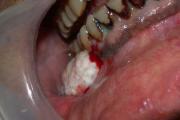

Crohni tõbi

limaskestal munajad moodustised (munakivi meenutavad)